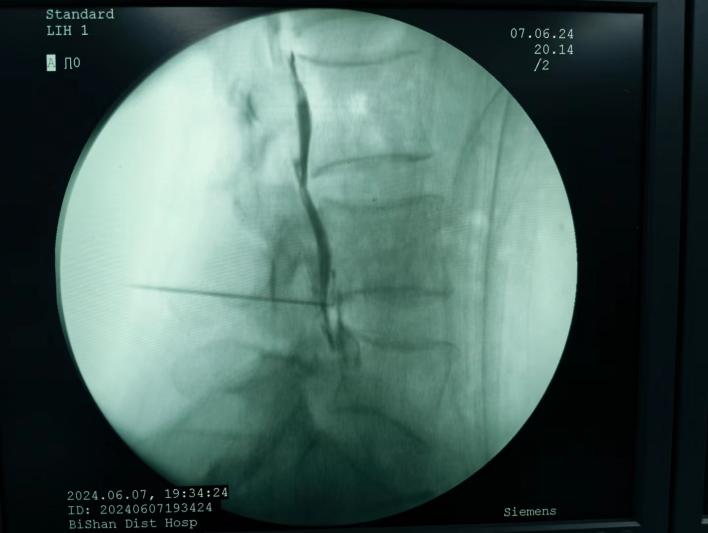

膠原酶椎間盤化學(xué)溶解術(shù),是在影像引導(dǎo)下(C型臂X線機(jī)或CT),將膠原酶準(zhǔn)確地注射到突出的椎間盤內(nèi)及其周圍,使突出的椎間盤溶解并吸收,解除其對神經(jīng)根的壓迫,進(jìn)而緩解癥狀。

椎間盤射頻消融術(shù)、膠原酶椎間盤化學(xué)消融術(shù)